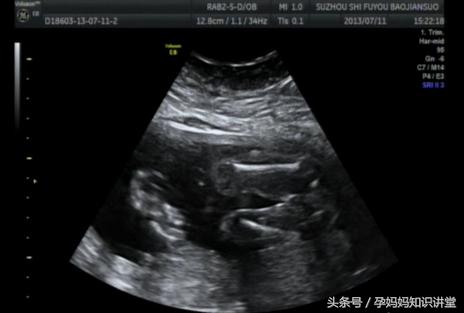

其一:看数据,如果长和宽的相差在一倍以上男宝宝可能性大。长和宽相等女宝宝可能性大。

其二:看形状,像茄子或长条状的是男宝宝可能性大,圆圆的是女宝宝可能性大。